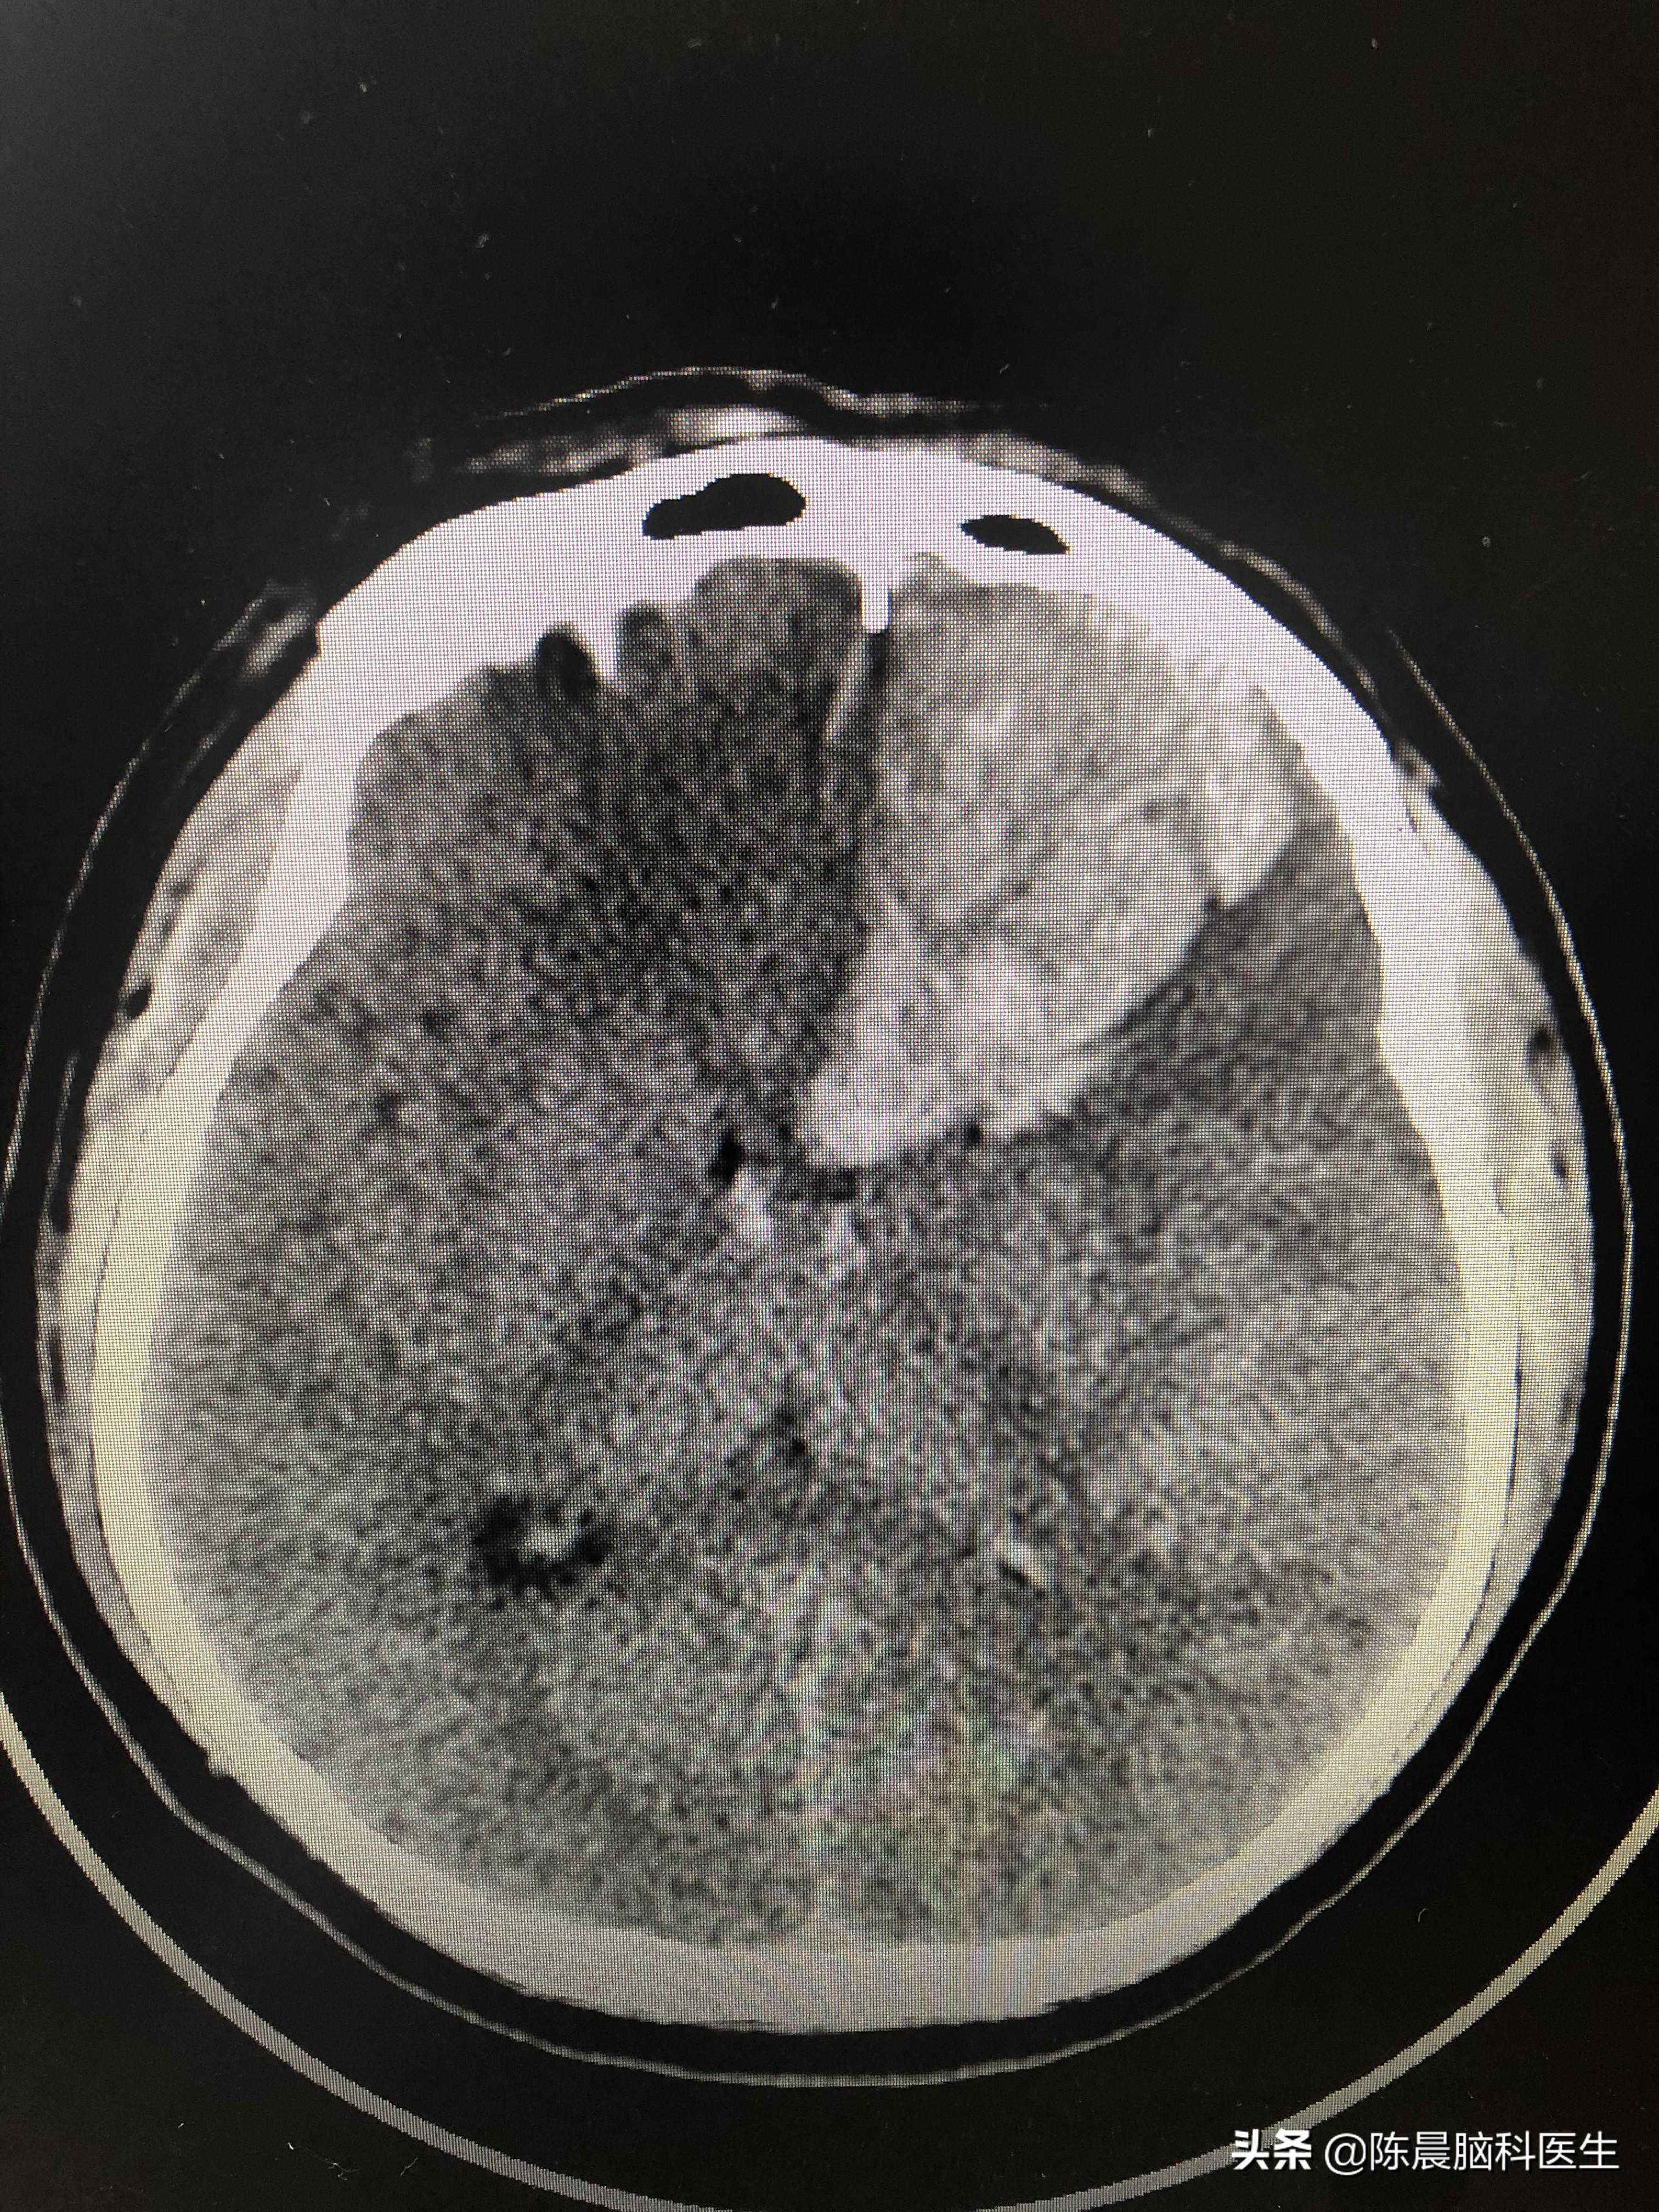

完了,于是,我赶紧又去帮他姐夫抬上他到了CT室,一做CT,不出所料,左侧额叶脑出血破入蛛网膜下腔,量大概有接近40ml。当时是早晨7点30,我紧急联系了我们神经外科的蒯主任,入住神经外科。

左侧额叶出血,量约40ml

后来根据出血的位置判断其是脑血管畸形,先行做了畸形的封堵,之后又做了开颅的血肿清除,还切除了部分的额叶,蒯主任他们一直忙到晚上10点多,才把他的两处问题解决了。

我这个朋友是脑出血破入蛛网膜下腔,以脑出血为主,但是因为存在畸形。如果当时直接开颅,由于满脑子是血,第一有可能找不到出血点,第二有可能出现二次出血。给他先行血管内介入治疗封闭了主要的动静脉畸形破溃处,再进行开颅清创,手术安全系数大增。